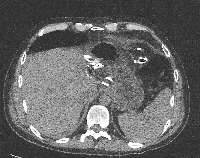

Πρόκειται για άνδρα ασθενή 45 ετών ο οποίος πριν από ένα χρόνο υποβλήθηκε σε κεντρική ηπατεκτομή για αδενοκαρκίνωμα αγνώστου πρωτοπαθούς εστίας. Έξι μήνες μετά την αρχική ηπατεκτομή και αφού είχε ολοκληρώσει τη μετεγχειρητική χημειοθεραπεία, διαπιστώθηκε ότι έφερε νέα μάζα στο 2ο και 3ο ηπατικό τμήμα (εικόνα 1), μακριά από το σημείο της πρώτης επέμβασης. Για άλλη μία φορά ο εκτεταμμένος έλεγχος (ενδοσκοπήσεις, αξονικές και μαγνητικές τομογραφίες, PET-CT scan) δεν ανέδειξε πρωτοπαθή εστία. Υποβλήθηκε σε έξι νέους κύκλους προεγχειρητικής χημειοθεραπείας (neoadjuvant) που οδήγησαν σε μερική ανταπόκριση. Πέντε εβδομάδες μετά τον τελευταίο χημειοθεραπευτικό κύκλο υποβλήθηκε σε αριστερή πλάγια επανηπατεκτομή (redo hepatectomy). Η μάζα αφαιρέθηκε in toto, σε υγιή όρια ηπατικού παρεγχύματος (εικόνα 2) αλλά με περιθώριο εκτομής μικρότερο του ενός cm. Για το λόγο αυτό εφαρμόστηκε εστιακή παρεγχυματική καταστροφή της επιφάνειας διατομής με μικροκύματα (εικόνα 3). Το εγχειρητικό πεδίο μετά την απομάκρυνση του παρασκευάσματος φαίνεται στην εικόνα 4. Την 5η μετεγχειρητική ημέρα πραγματοποιήθηκε αξονική τομογραφία που δεν ανέδειξε παθολογικά ευρήματα (εικόνα 5). Ο ασθενής έλαβε εξιτήριο την 6η μετεγχειρητική ημέρα.